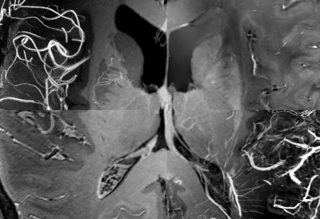

Die Überlagerung von mehreren ultra-hochaufgelösten MRT-Kontrasten zeigt die Anatomie und Gefäßversorgung des menschlichen Hirns (c) Falk Lüsebrink / Universität Magdeburg.Die Überlagerung von mehreren ultra-hochaufgelösten MRT-Kontrasten zeigt die Anatomie und Gefäßversorgung des menschlichen Hirns. (Bild: Falk Lüsebrink / Universität Magdeburg)

Bild 1 // Urheber: Falk Lüsebrink / Universität Magdeburg // Bildunterschrift: Die Überlagerung von mehreren ultra-hochaufgelösten MRT-Kontrasten zeigt die Anatomie und Gefäßversorgung des menschlichen Hirns.